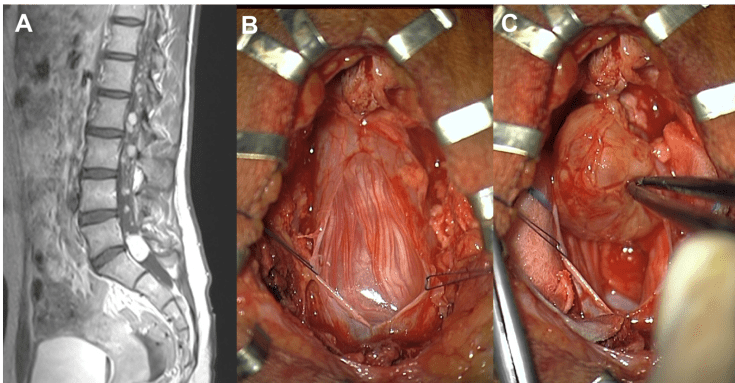

l’épendymome myxo-papillaire

c’est un type nettement distinct de l’épendymome intramédullaire, qui est de grade 2 et souvent dans le cadre de la NF2, ce qui n’est pas le cas du myxo-papillaire.

grade I de l’OMS, celui-ci mérite mal sa réputation de bénignité, car il existe un risque réel de récidive locale voire métastatique.

la chirurgie vise à l’exérèse complète ; elle est suivie d’une radiothérapie.